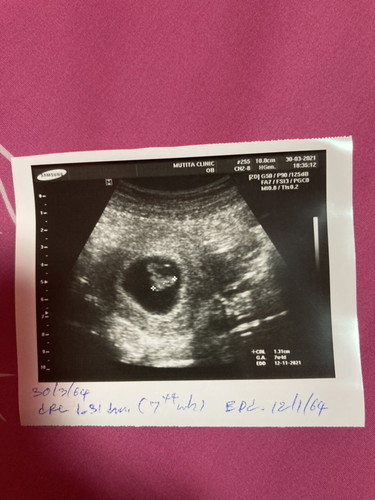

มีแล้วค่ะ ที่เห็นในวงนั้นแหละค่ะ นอนขดเป็นกุ้งเลย

มีตัวน้องรึยังค่ะแบบนี้